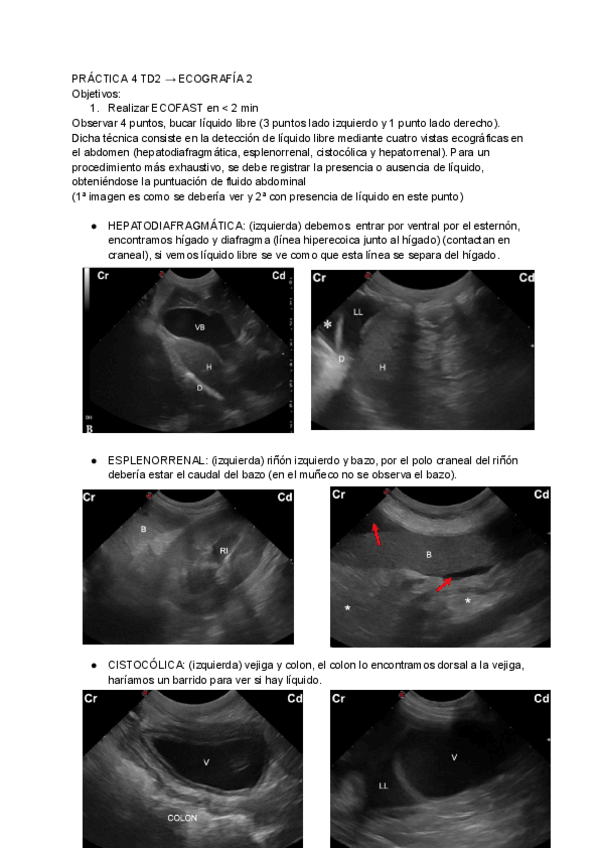

He publicado nuevos practicas de 3º Técnicas de diagnóstico clínico II (Diagnóstico por imagen): PRACTICA-4-TD2-ECOGRAFIA-2.pdf

3 páginas